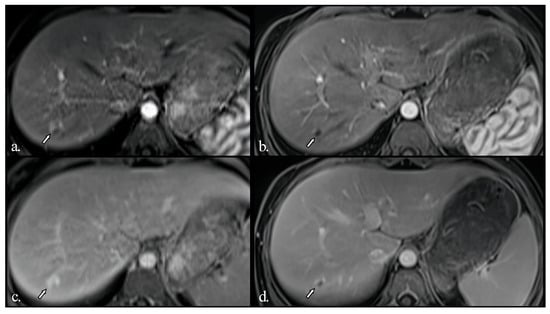

In addition to standardized lateral cephalometric radiographs, comprehensive assessment using dental cone-beam computed tomography (CBCT) and CT has become commonplace in the diagnosis and treatment of jaw deformities. Simulation based on cephalometr...